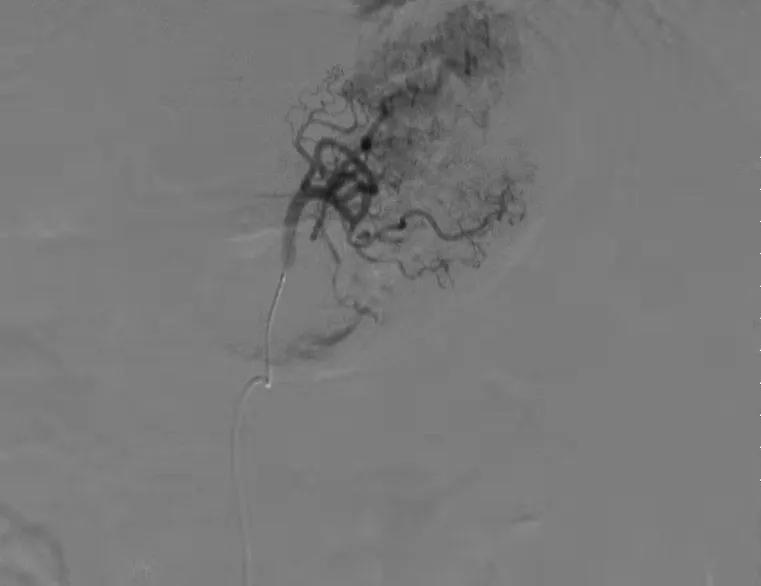

精确插管到胃左动脉

栓塞后胃左动脉闭塞,血流中断